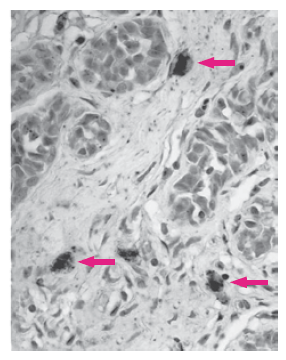

Les vaisseaux tumoraux sont caractérisés par une morphologie anormale : ils sont trop branchés et aussi perméables, car ils sont dépourvues de péricytes et de cellules musculaires lisses et possèdent une membrane basale irrégulière avec un revêtement endothélial irrégulier. Ils sont ainsi fortement dysfonctionnels dans leurs propriétés de barrière et de transport.

Cela aboutit à une hétérogénéité d’oxygénation dans les tumeurs qui contribue à l’hétérogénéité phénotypique des cellules tumorales (Barnabeu et al., 2020).

là où les vaisseaux sanguins (taches bleues) assurent une bonne oxygénation, le

la tumeur apparaît noire. En revanche, dans les zones de mauvaise vascularisation et avec une hypoxie modérée, une enzyme anhydrase carbonique est exprimée (révélée en rouge orange), tandis que dans les zones d’hypoxie importante, le colorant pimonidazole est détecté (vert). Le chevauchement entre ces deux marqueurs apparaît en orange. Des zones de nécrose, situées encore plus loin du système vasculaire tumoral, sont indiqués par « N ». Source : https://aacrjournals.org/cancerres/article/62/23/7066/509392/Pimonidazole-Binding-and-Tumor-Vascularity-Predict